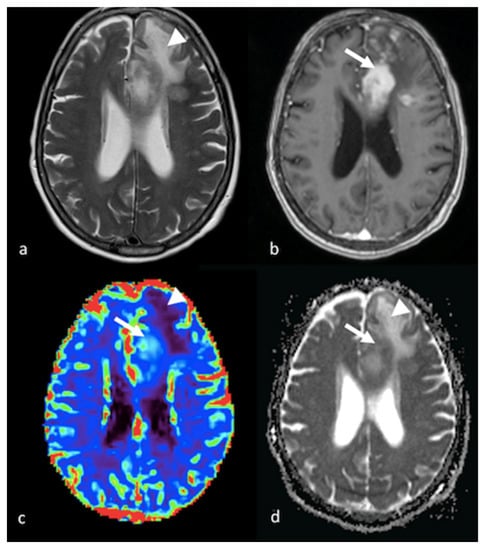

3.3.1. Dynamic Susceptibility Contrast-Enhanced Perfusion

- Halshtok Neiman, O.; Sadetzki, S.; Chetrit, A.; Raskin, S.; Yaniv, G.; Hoffmann, C. Perfusion-weighted imaging of peritumoral edema can aid in the differential diagnosis of glioblastoma mulltiforme versus brain metastasis. Isr. Med. Assoc. J. 2013, 15, 103–105. [Google Scholar] [PubMed]

- Neska-Matuszewska, M.; Bladowska, J.; Sasiadek, M.; Zimny, A. Differentiation of glioblastoma multiforme, metastases and primary central nervous system lymphomas using multiparametric perfusion and diffusion MR imaging of a tumor core and a peritumoral zone-Searching for a practical approach. PLoS ONE 2018, 13, e0191341. [Google Scholar] [CrossRef]

- Askaner, K.; Rydelius, A.; Engelholm, S.; Knutsson, L.; Latt, J.; Abul-Kasim, K.; Sundgren, P.C. Differentiation between glioblastomas and brain metastases and regarding their primary site of malignancy using dynamic susceptibility contrast MRI at 3T. J. Neuroradiol. 2019, 46, 367–372. [Google Scholar] [CrossRef]

- Blasel, S.; Jurcoane, A.; Franz, K.; Morawe, G.; Pellikan, S.; Hattingen, E. Elevated peritumoural rCBV values as a mean to differentiate metastases from high-grade gliomas. Acta Neurochir. 2010, 152, 1893–1899. [Google Scholar] [CrossRef] [PubMed]

- Mangla, R.; Kolar, B.; Zhu, T.; Zhong, J.; Almast, J.; Ekholm, S. Percentage signal recovery derived from MR dynamic susceptibility contrast imaging is useful to differentiate common enhancing malignant lesions of the brain. AJNR Am. J. Neuroradiol. 2011, 32, 1004–1010. [Google Scholar] [CrossRef]

- Ma, J.H.; Kim, H.S.; Rim, N.J.; Kim, S.H.; Cho, K.G. Differentiation among glioblastoma multiforme, solitary metastatic tumor, and lymphoma using whole-tumor histogram analysis of the normalized cerebral blood volume in enhancing and perienhancing lesions. AJNR Am. J. Neuroradiol. 2010, 31, 1699–1706. [Google Scholar] [CrossRef]